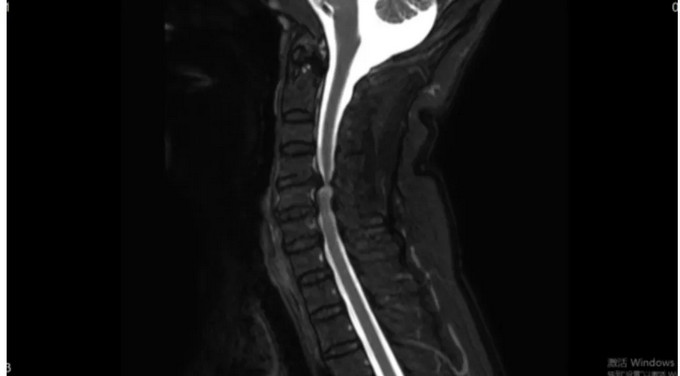

術后影像

頸椎CT矢狀位

頸椎CT橫斷位 可以看到突出的骨贅已被切除

頸椎MRI矢狀位 頸神經(jīng)壓迫程度明顯減輕